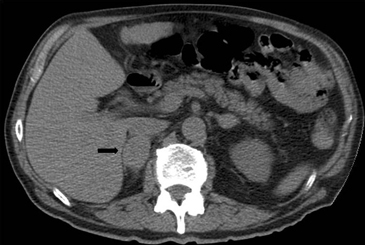

Figura 6. Lesión homogénea, de contornos bien delimitados (flecha) visualizada en tomografía computada sin contraste realizada en contexto de estudio de diseminación de cáncer mamario. A pesar de los caracteres morfológicos aparentemente benignos, se demostró que la lesión correspondía a una localización secundaria.